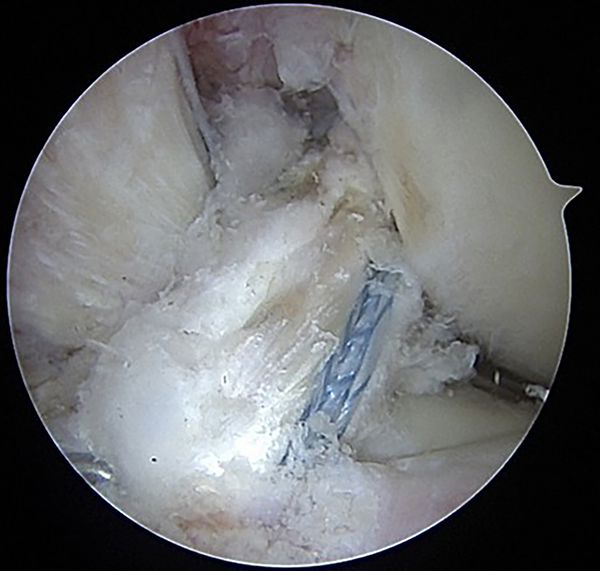

Es importante destacar que el IB en ningún momento compite con el injerto de reconstrucción del LCA. En flexión, el FiberTape® se relaja. Por el contrario, cuando la rodilla se extiende se puede observar como el FiberTape® se tensa para evitar sobreconstreñir la rodilla o competir con la integración del injerto, y así cumplir su función de cinturón de seguridad (fig. 6).

Figura 6: A-B) Visualización artroscópica en 90° de flexión. Plástica del LCA con aloinjerto de tibial anterior, InternalBracetm más laxo. C-D) Visualización en extensión, InternalBracetm con buena tensión.

Luego de la fijación tibial se realizó visualización final de la reconstrucción del LCA y refuerzo con InternalBracetm (fig. 7).

Figura 7: Visualización final de la reconstrucción del LCA con aumentación InternalBracetm.